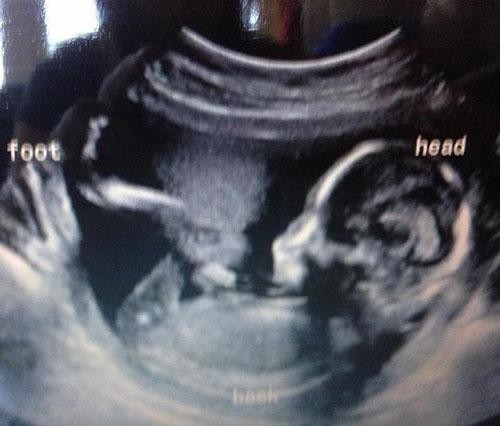

Bebeklerinin bu ilk görüntüsüyle anne-babalar şoke oldu!

El işareti yapan bebek